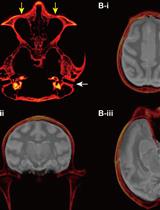

通过手持式注射将化学遗传学腺相关病毒载体靶向递送至猕猴皮质沟区域

Targeted Delivery of Chemogenetic Adeno-Associated Viral Vectors to Cortical Sulcus Regions in Macaque Monkeys by Handheld Injections

KO Kei Oyama

YN Yuji Nagai

TM Takafumi Minamimoto

1697 Views

Dec 5, 2023

Recent advancements in chemogenetic tools, such as designer receptors exclusively activated by designer drugs (DREADDs), allow the simultaneous manipulation of activity over a specific, broad brain region in nonhuman primates. However, the introduction of DREADDs into large and complexly shaped cortical sulcus regions of macaque monkeys is technically demanding; previously reported methods are time consuming or do not allow the spatial range of expression to be controlled. In the present report, we describe the procedure for an adeno-associated viral vector (AAV2.1) delivery via handheld injections into the dorsolateral prefrontal cortex (Brodmann’s area 9/46) of macaque monkeys, with reference to pre-scanned anatomical magnetic resonance images. This procedure allows the precise delivery of DREADDs to a specific cortical region.Key features• This article describes the procedures for injecting viral vectors encoding functional proteins for chemogenetic manipulation into targeted cortical sulcus regions.• The protocol requires magnetic resonance imaging for the accurate estimation of the injection sites prior to surgery.• Viral vector solutions are injected using a handheld syringe under microscopic guidance.• This protocol allows for the precise introduction of designer receptors exclusively activated by designer drugs (DREADDs) to large and complex cortical regions.